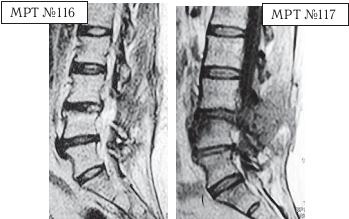

На МРТ № 116 (в режиме Т2-ВИ) и МРТ № 117 (в режиме Т1-ВИ) той же пациентки наблюдается состояние через три месяца после хирургического вмешательства.

На МРТ № 117 в режиме Т1-ВИ отчётливо видно, что был прооперирован межпозвонковый диск в сегменте LIII—LIV вместо диска в сегменте LIV-LV В передней части тела позвонка LIV наблюдается очаг воспаления, реактивный асептический дисцит (частая и можно сказать естественная реакция тканей на операцию, вследствие развития аутоиммунных реакций).